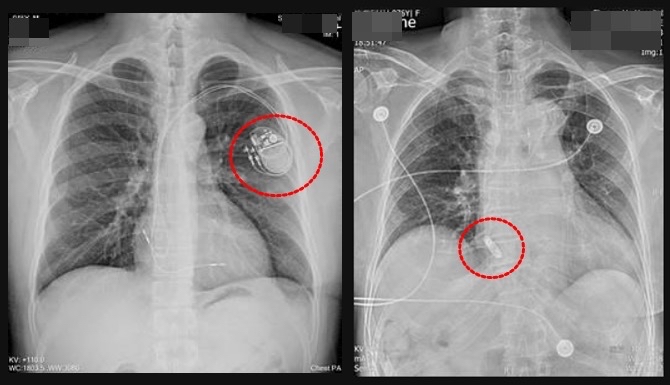

值得注意的是,傳統心臟節律器包括電池和導線,導線一端埋在心肌,一端連結電池,此技術已成熟且多有健保給付。但導線可能增加瓣膜損傷風險,也有掉落的可能,且因電池需埋於胸前皮下,會有胸前肌肉、皮膚的感染風險,病人也難進行大幅揮臂動作。如高爾夫球、網球或需頻繁使用肩關節與胸肌的球類運動,或是鍛鍊上肢的重量訓練也可能受限,且須避免將手機放置於患側胸前口袋,以免影響節律器運作。

而無導線心臟節律器體積如膠囊,可直接置放於右心房或右心室內,不需導線及胸前皮下囊袋,大幅降低感染、氣胸等併發症,外觀上亦不易察覺,對生活影響降至最低;惟無導線節律器並非適用於所有病患,仍須由醫師專業評估。過往無導線心臟節律器只有放在右心室內的選項,直至去年8月經過衛生福利部核可後,右心房的無導線心臟節律器才得以使用。